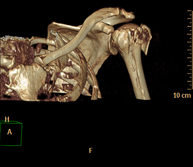

- Osteoarticular- TC Hombro Exploración radiológica que mediante un sistema de rayos X y detectores que giran alrededor del paciente, reconstruyendo las imágenes por ordenador (TC Multidetector), permite el estudio de huesos, músculos y articulaciones del hombro. Exploración radiológica que mediante un sistema de rayos X y detectores que giran alrededor del paciente, reconstruyendo las imágenes por ordenador (TC Multidetector), permite el estudio de huesos, músculos y articulaciones del hombro.

- TC Codo Exploración radiológica que mediante un sistema de rayos X y detectores que giran alrededor del paciente, reconstruyendo las imágenes por ordenador (TC Multidetector), permite el estudio de huesos, músculos y articulaciones del codo. Exploración radiológica que mediante un sistema de rayos X y detectores que giran alrededor del paciente, reconstruyendo las imágenes por ordenador (TC Multidetector), permite el estudio de huesos, músculos y articulaciones del codo.

- TC Mano – muñeca Exploración radiológica que mediante un sistema de rayos X y detectores que giran alrededor del paciente, reconstruyendo las imágenes por ordenador (TC Multidetector), permite el estudio de huesos, músculos y articulaciones de mano y muñeca. Exploración radiológica que mediante un sistema de rayos X y detectores que giran alrededor del paciente, reconstruyendo las imágenes por ordenador (TC Multidetector), permite el estudio de huesos, músculos y articulaciones de mano y muñeca.

- TC Pelvis ósea Exploración radiológica que mediante un sistema de rayos X y detectores que giran alrededor del paciente, reconstruyendo las imágenes por ordenador (TC Multidetector), permite el estudio de huesos, músculos y articulaciones de la pelvis. Exploración radiológica que mediante un sistema de rayos X y detectores que giran alrededor del paciente, reconstruyendo las imágenes por ordenador (TC Multidetector), permite el estudio de huesos, músculos y articulaciones de la pelvis.

- TC Caderas Exploración radiológica que mediante un sistema de rayos X y detectores que giran alrededor del paciente, reconstruyendo las imágenes por ordenador (TC Multidetector), permite el estudio de huesos, músculos y articulaciones de la cadera. Exploración radiológica que mediante un sistema de rayos X y detectores que giran alrededor del paciente, reconstruyendo las imágenes por ordenador (TC Multidetector), permite el estudio de huesos, músculos y articulaciones de la cadera.